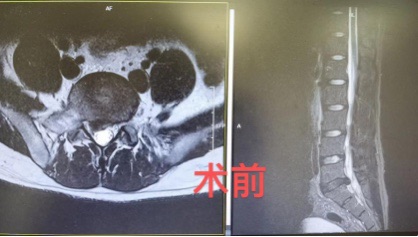

外地来沪工作的方先生(化名)今年30岁,是一名建筑设计师,工作很忙,经常加班,下工地等。有一天,他隐隐感觉右腿痛,行走有些困难,但没太在意,两天后下班回到宿舍方先生感觉右腿痛严重了,休息一晚没有好转,第二天,他到附近一所大医院去看门诊,拍了右腿、右膝的X光片,没有发现问题,开药后,回家休息。 又过了一天,方先生的右腿剧痛,下不了床,且翻身困难。同事送往上海德济医院急诊,德济医院骨科当值医生询问病史,并进行查体后,判断方先生是右侧坐骨神经痛,当即安排腰椎核磁共振检查。核磁共振检查结果:腰5骶1椎间盘偏右侧突出,伴部分髓核脱出,相应的神经根显示不清,于是立即安排住院。方先生和家人非常感激德济的医生为他明确了诊断。 上海德济医院骨科何博主任向方先生一家阐述了手术治疗的必要性。腰椎间盘突出症虽然大多时候属于慢性疾病,但方先生这例属于腰椎间盘突出症急性发作,神经压迫的症状体征非常典型,保守治疗的意义不大,还可能造成更严重的后果,需要外科手术干预。 方先生和家人多方咨询并且百度了各种手术方式优缺点。最终决定手术治疗,并为杜绝复发的可能,要求同时做融合术。 骨科何博主任、刘春主任带领手术团队周末加班为方先生行“腰椎间盘突出髓核摘除,cage植入,椎弓根螺钉固定术”。手术非常顺利,方先生说:术后当天就感觉右腿就明显疼痛减轻,可以抬起了。方先生术后第二天就下床活动,从外地赶来的父母对德济医院骨科团队非常感激!

△术前影像图